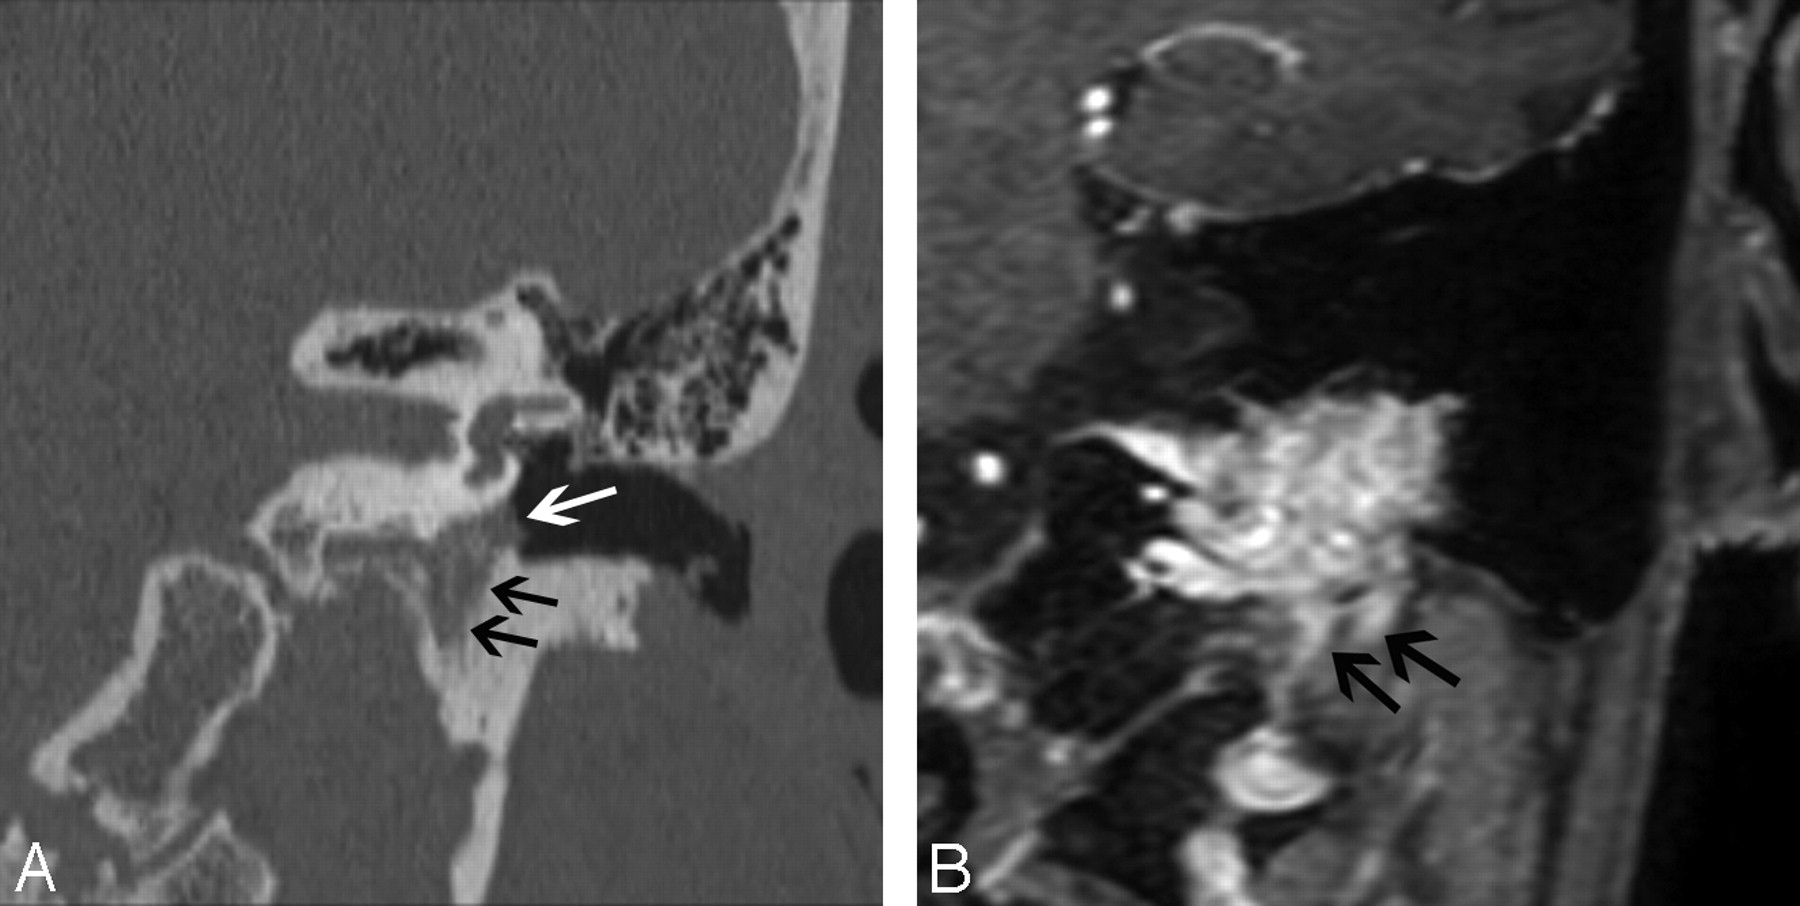

Glomus jugulare paragangliomas arise in the jugular bulb and can aggressively erode the bone of the lateral jugular bulb to extend toward the middle ear. On CT, the presence of permeative bone erosion of the superolateral jugular foramen wall is an important diagnostic clue (Fig 9A). Jugular spine erosion is also common. On MR imaging, large flow voids interspersed with high-signal-intensity parenchyma provide a characteristic “salt and pepper” appearance. Enhanced MR imaging may provide a better estimate of the extent of the mass (Fig 9B). Angiography shows enlarged feeding vessels, a prolonged and intense vascular blush, and early draining veins from arteriovenous shunting.

Glomus jugulotympanicum in 45-year-old woman who presented with left-sided pulsatile tinnitus. A, Coronal CT image demonstrates soft-tissue attenuation projecting in the hypotympanum (white arrow). There is permeative osseous destruction in the left jugular foramen (black arrows), providing a clue as to the origin of the mass in the left jugular foramen. B, Enhanced coronal MR image better demonstrates the true extent of the mass within the left jugular foramen (black arrows).